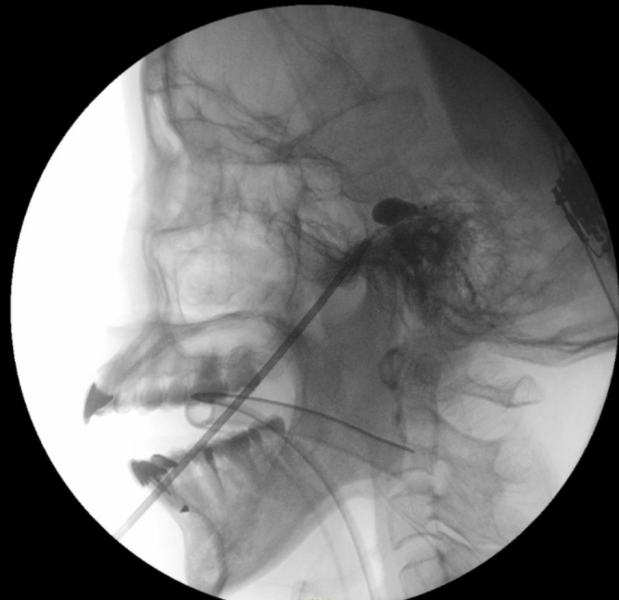

「經皮球囊壓迫術」屬微創介入技術,用於緩解與三叉神經相關的疼痛。而三叉神經負責面部感覺,當其功能異常時,會引發劇烈的面部疼痛。醫生會經面頰穿刺將微型球囊導管置入顱底的三叉神經節,用顯影劑擴張球囊,壓迫痛覺神經纖維。術中通過透視影像確認球囊呈梨形外觀以確保位置準確,從而精準阻斷痛覺傳導。

瑪麗醫院麻醉、疼痛和圍術期醫學顧問醫生陳智榮醫生解釋:「經皮球囊壓迫術的引入,讓我們在處理複雜面部疼痛方面邁出重要一步。傳統的射頻消融術(Radiofrequency Ablation,RFA)需要患者保持清醒配合感覺測試以定位疼痛點;經皮球囊壓迫術全程在麻醉下進行,患者體驗更舒適。其獨特優勢在於單次治療即可覆蓋三叉神經眼支、上頜支與下頜支的廣泛痛區。」